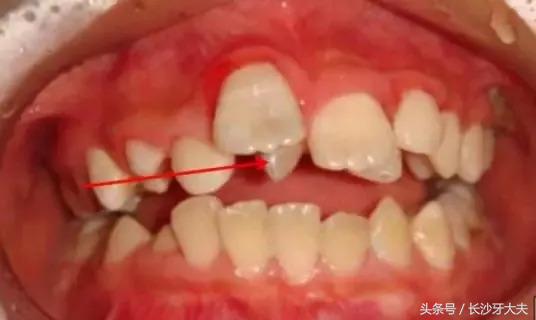

讲了这么多,给大家看一例真实的案例吧:由于多生牙占据了正常门牙应在的位置,两颗门牙还没长出来就被迫分开了很大的距离。

只有去除多生牙的阻碍,以后才可以进行矫正排齐门牙,所以我还是摆脱不了被拔除的命运。